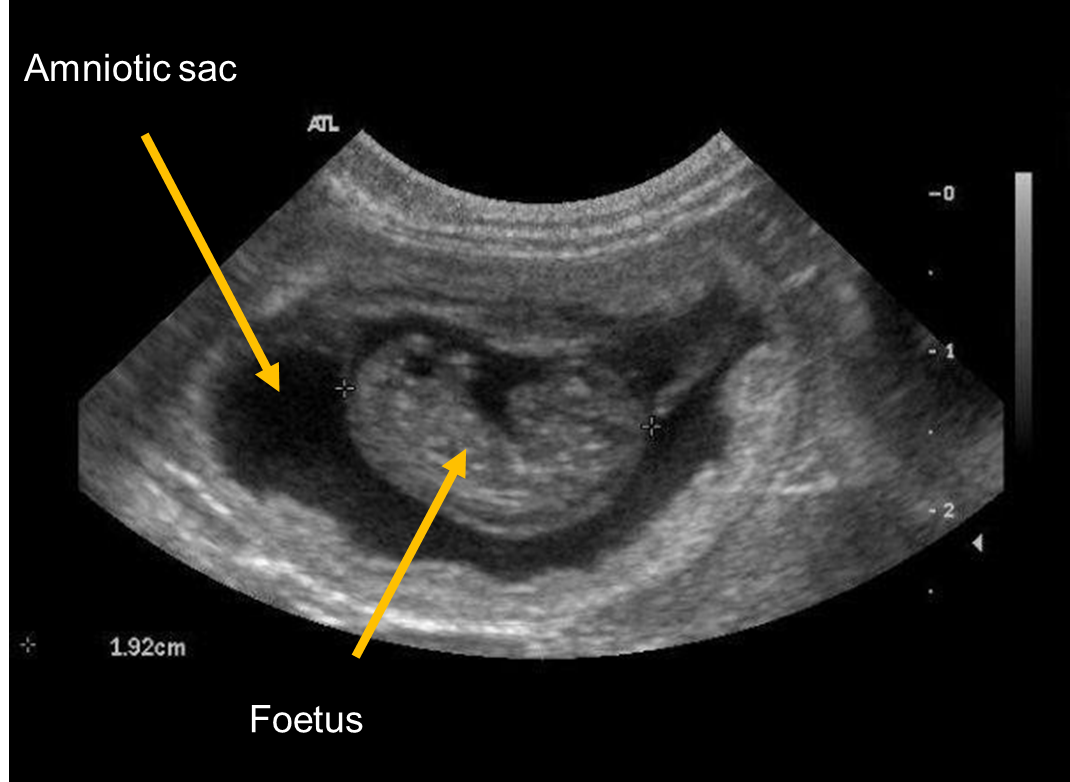

What diagnostic method can we use for pregnancy from 25 days onwards?

Ultrasound —> smaller dogs with front legs in air to help drop uterus caudally (makes imaging easier)

Heartbeat can be detected from 25 days onwards